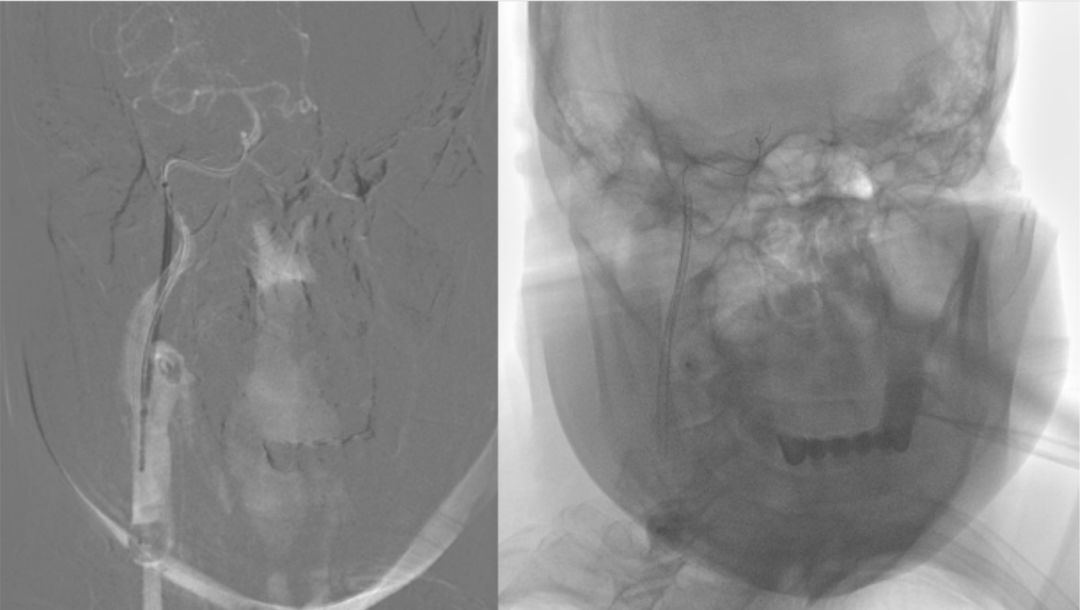

撤出PILOT 50微导丝,沿MOMA送入Synchro微导丝(0.014"x190 cm)+Headway 21微导管至右侧颈内动脉C1段,撤出微导管,将Synchro微导丝送入右侧大脑中动脉M1段,沿Synchro微导丝送入WALLSTENT支架(9 mmx50 mm)至C1段末端,定位准确后充盈MOMA球囊释放支架成功,抽瘪MOMA球囊,撤出支架输送装置。造影显示支架完全覆盖C1狭窄段(图9)。

图9

与血管壁贴合良好,无急性血栓形成。远端未放支架血管残余狭窄仍较重,沿Synchro微导丝送入Ultra-soft球囊(2.5 mmX20 mm)球囊,使用MOMA近端保护技术,依次由远到近对残余狭窄段进行扩张(图10),造影显示残余狭窄段较前改善。观察10 min,行右侧颈总动脉正侧位造影,显示右侧大脑中、前动脉及分支动脉显影良好,可见支架内血流通畅,无急性血栓形成(图11)。

图10

图11